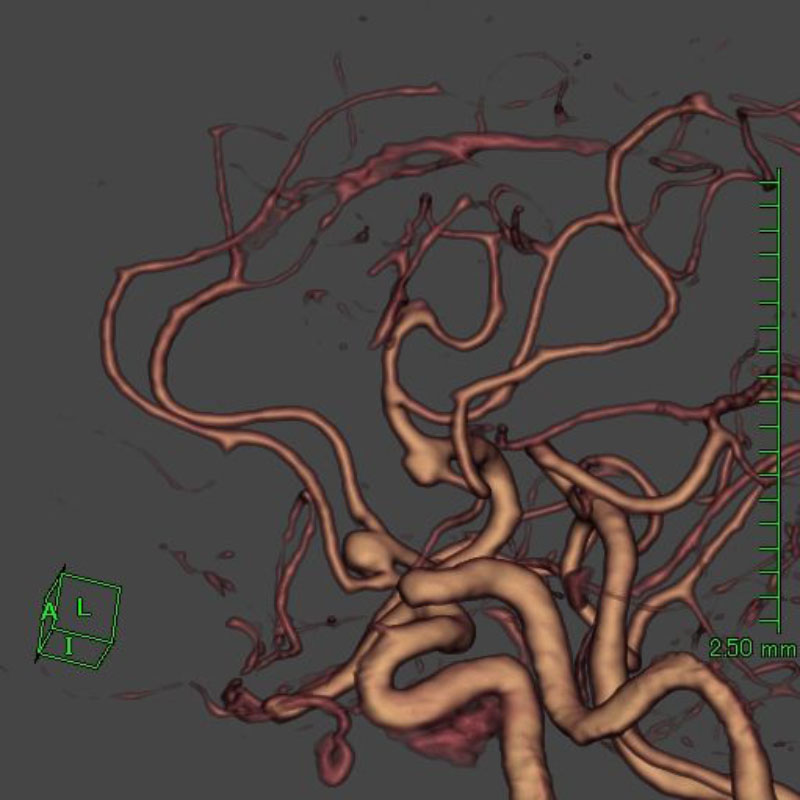

手術前

クリップ前

クリップ後

手術後

右中大脳動脈瘤

クリッピング術

術後血管撮影